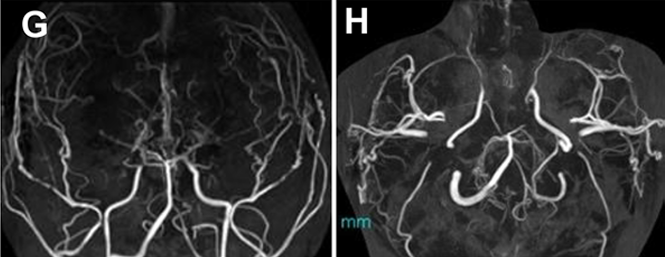

搭桥术后患者康复,没有明显的残疾。然而,在手术复查和基因诊断后5年,他出现了短暂性脑缺血发作,伴有反复的左偏瘫。MRA 显示大脑中前动脉的缺损和大脑后动脉的进行性狭窄(图G 、H)。

第二次手术在右大脑中动脉处另设旁路,以右枕动脉为供体动脉,术后太一状态良好。

图G&H:发病5年后进行的MRA显示主要颅内动脉狭窄的显着进展。